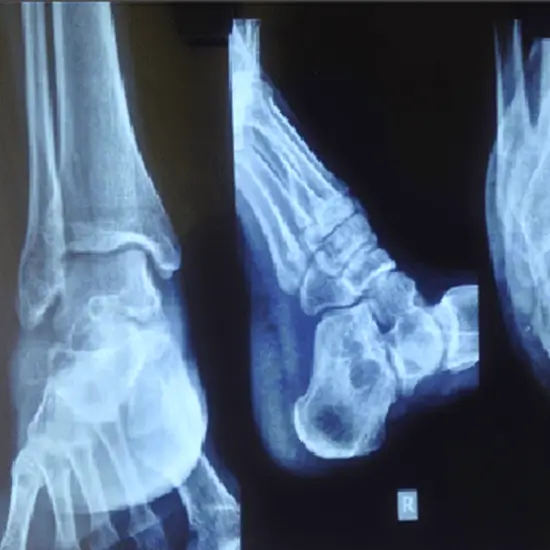

The LAT view of the calcaneus (the bone of the heel) is part of the two-view calcaneus series. This is how the calcaneus, talonavicular, talonavicular, and talonavicular joints are evaluated. If your heel hurts a lot, is red, or swells up, your doctor may order an X-ray of both Calcaneus in lateral view to find out why.